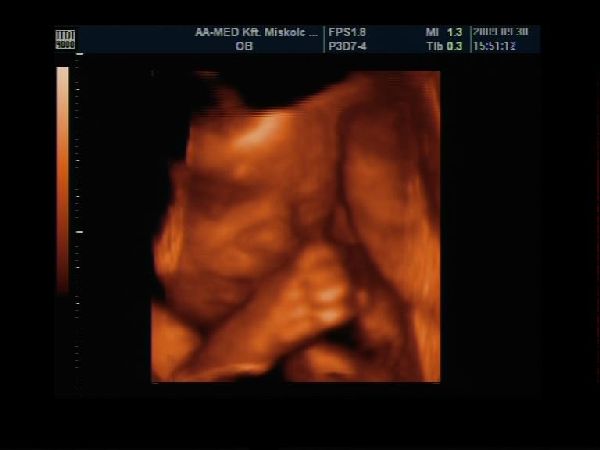

Kicsi fiam 27hetesen

Kép

Épp gondolkodik :)